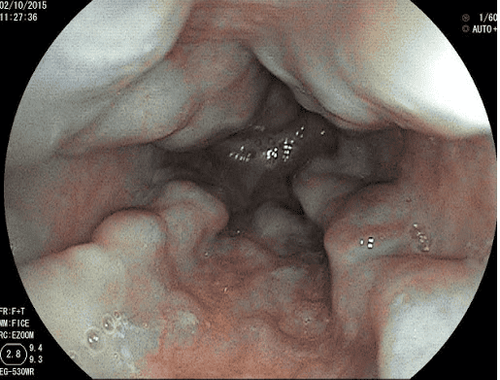

- Nội soi thực quản – dạ dày: Phương pháp này được chỉ định khi nghi ngờ bệnh nhân bị tăng áp lực tĩnh mạch cửa với hình ảnh giãn tĩnh mạch thực quản.